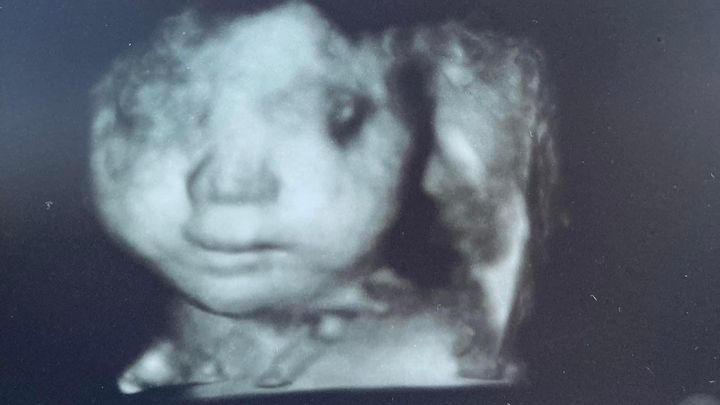

Nikki is an amazing woman, mom and colleague. She was excited to learn she was pregnant with her first daughter (who will be named Jaliyah Nicole), but tragically the baby has trisomy 18. This condition is almost always fatal for the child, who is due in December. Nikki is a single mom to three boys who rely on her, and serves the public by defending individuals from evictions in her job as an attorney.